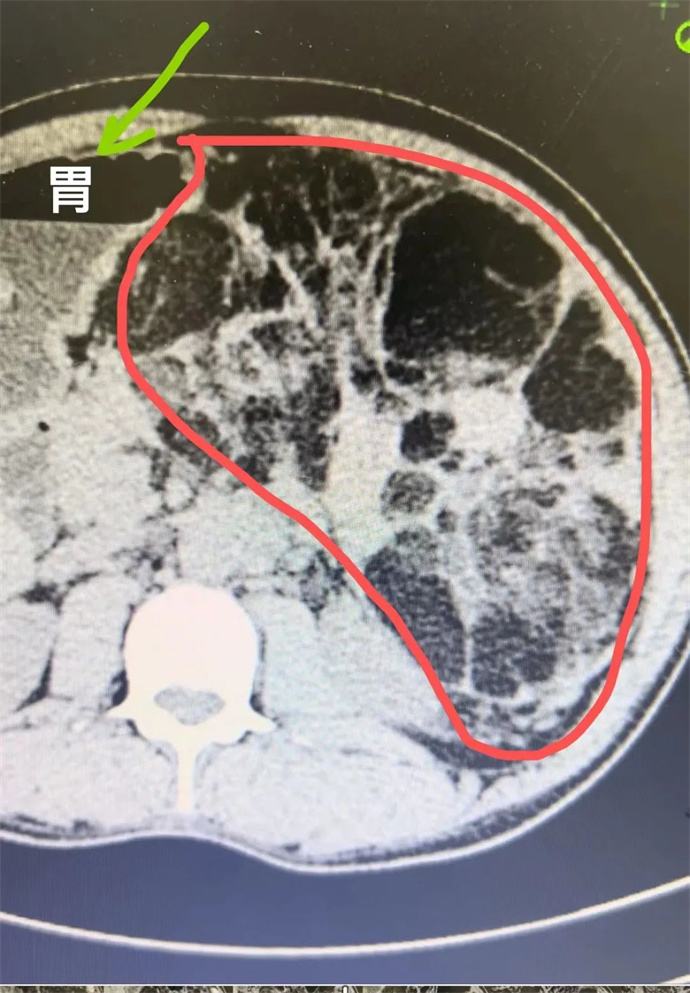

近日,我院泌尿外科會診一位四十多歲男性患者時發現,該患者腹部有一巨大腫瘤,直徑近30cm,已將該患者胃、胰腺、脾臟及部分腸管擠壓移位,且腫瘤內可見大量動靜脈畸形,存在極大的出血風險,一旦出血將危及患者生命,客觀告知患者及家屬相關病情后,患者及家屬憂心忡忡,基本的日常活動都心有畏懼,充分溝通后,轉入泌尿外科,擬行手術治療。

轉入泌尿外科后,強永春主任及專家組積極術前準備,仔細閱片,充分討論,明確此腫瘤來源為左側腎臟,多考慮為腎臟血管平滑肌脂肪瘤,俗稱“錯構瘤”。周莉護士長帶領護理組通過傾聽、解釋、鼓勵、提供支持、建立信任等來安撫患者的憂心忡忡,幫助他們更好地應對疾病。科學、客觀的指導患者的術后康復。

錯構瘤屬于良性腫瘤,絕大多數錯構瘤患者沒有明顯的癥狀,一些比較大的錯構瘤,可能會出現局部壓迫癥狀或壓迫周圍臟器,出現相應的癥狀。腎錯構瘤最大的危害在于,體積較大的錯構瘤突然破裂時,患者會出現腰腹疼痛和血尿等癥狀,嚴重的大出血患者可以在腹部觸及到包塊,甚至有休克癥狀。因此當腫瘤直徑大于4cm時,一般會積極建議手術,減少自發破裂的風險。但該患者平素未行體檢,腫瘤已近30cm,因此貿然手術處理存在巨大的風險。

強永春主任帶領泌尿外科團隊積極協調,提前預約腫瘤介入王忠主任,于術前行介入栓塞,減少術中出血風險;同時聯系輸血科提前術中備血;因腫瘤已侵及腎臟大部及腎臟血管,無法保留腎單位行腎部分切除,故先側臥位行后腹腔鏡下微創手術,游離并處理腎臟血管,確保切除時安全,再仰臥位行錯構瘤及腎臟切除;充分準備后,手術按預定方案如期進行,歷時6小時,成功拆除“定時炸彈”。目前患者已出院恢復了日常工作。